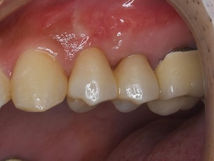

症例① 2ヶ所のパーフォレーションを修復して抜歯を回避した症例

初診時年齢:27歳

性別:女性

主訴:根の病気を治したい

治療期間:3ヶ月

費用:22万円

治療のリスク:術後の腫れ、痛み

副作用:-

治療内容/装置:精密根管治療(大臼歯)、オールセラミッククラウン

根分岐部側に広範囲なストリッピングパーフォレーションが確認できる。

根尖側にも湾曲根管を直進してできたパーフォレーションがある。

他院にて根管治療中の方で、根管治療が終わったのに痛みとサイナストラクト(旧フィステル)が

無くならないとのことで来院

手前側の1根管だけで2ヶ所のパーフォレーションがあり、MTAにて根管充填がされていた。

MTAを全て除去し、通法に従い根管治療後、MTAにて根管充填を行なった。

根管充填後、既にエックス線上にて病変の縮小を認めた。